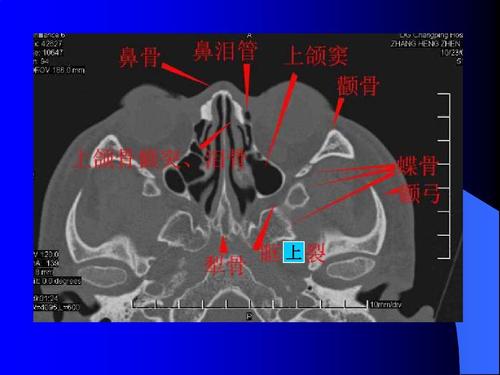

鼻窦ct轴位解剖图解

鼻窦CT解剖图谱

鼻窦CT解剖图谱,鼻窦炎解剖图